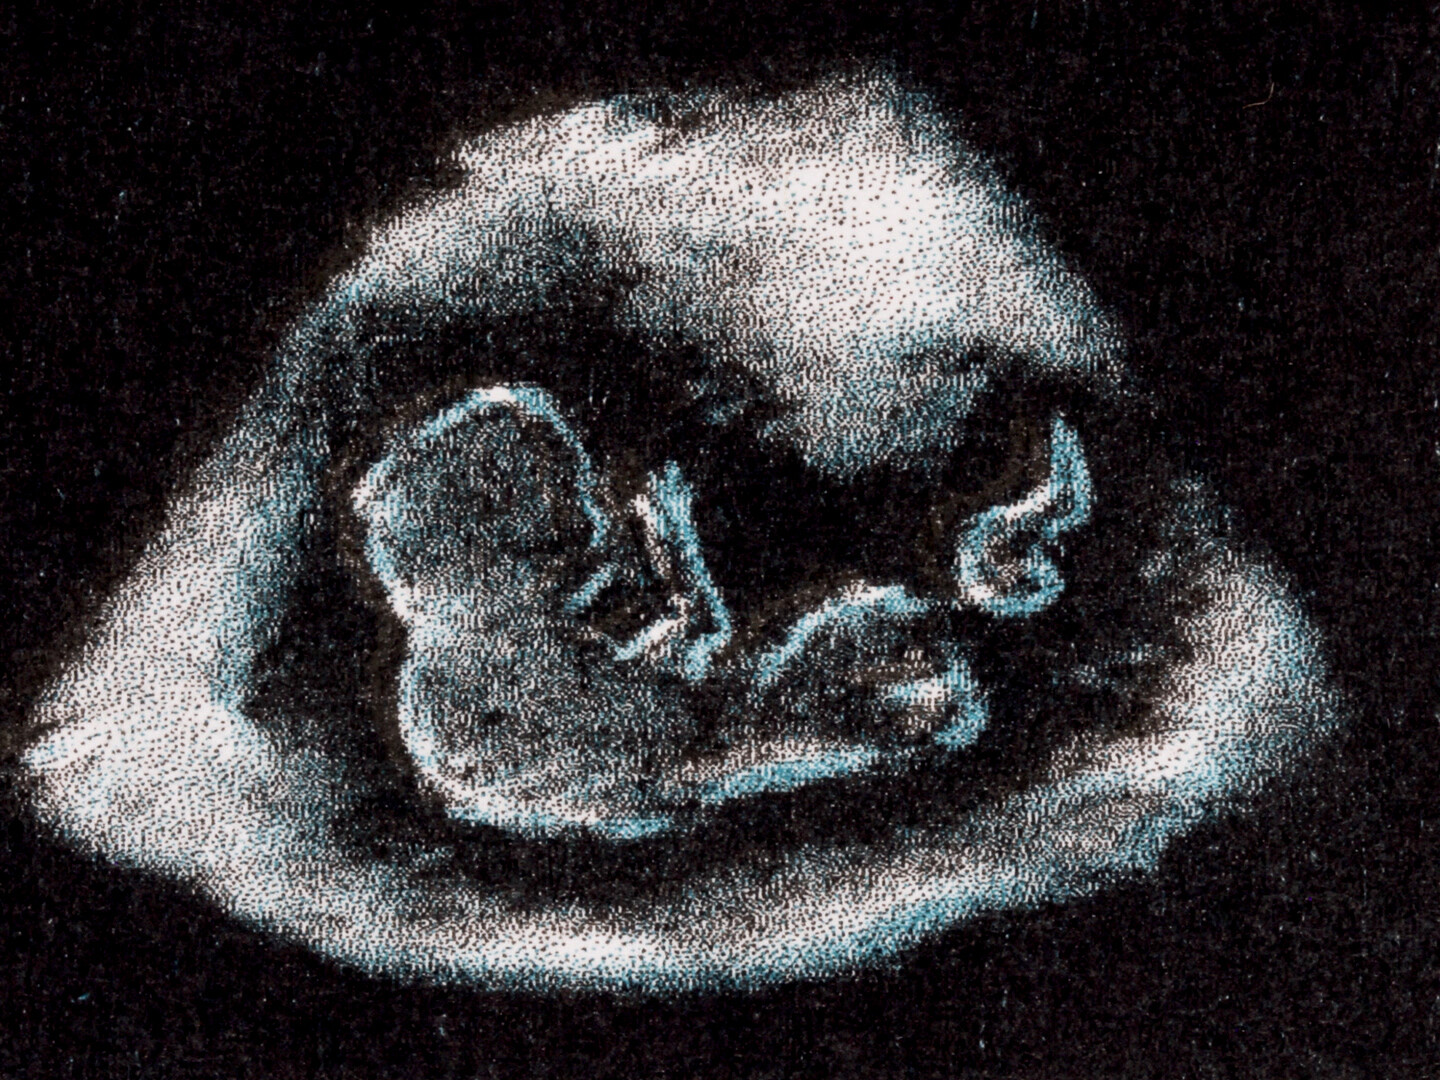

Un documentaire expérimental qui révèle les faits et les fantasmes de l’histoire des tests de grossesse des années 1930 à 1960, basés sur l’utilisation de grenouilles et de lapins vivants. Ces tests ont révolutionné le monde : ils ont élargi notre compréhension des hormones, offert aux femmes davantage de choix en matière de reproduction et provoqué une crise écologique, décimant certaines populations d’amphibiens.

An experimental documentary that reveals both the facts and fantasies of the history of pregnancy tests from the 1930s-60s which relied on the use of live frogs and rabbits. These pregnancy tests changed the world: they expanded our understanding of hormones, gave women more reproductive choice, and caused ecological crisis- decimating certain amphibian populations.